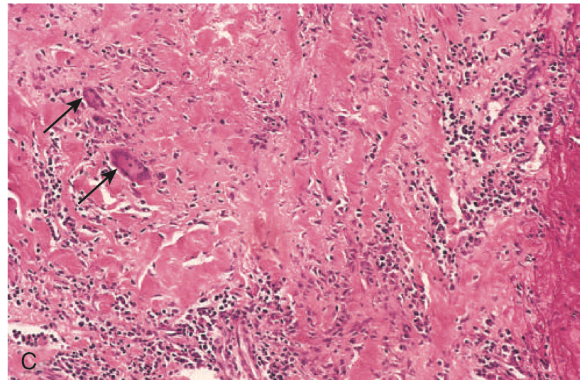

Takayasu arteritis

• histo illustrating destruction and fibrosis of the arterial media associated with mononuclear infiltrates and giant cells (arrows)